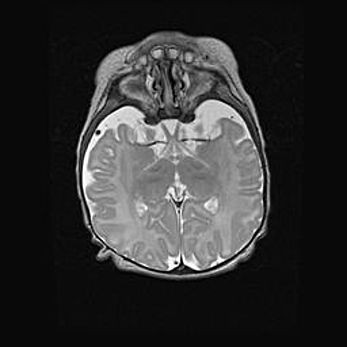

Подострая гематома правой гемисферы мозжечка.

Наружная гидроцефалия.

Возраст: 15 дней

Вес: 3100 г

Пол: женский

Окружность головы: 37 см

Срок гестации: 35-36 недель

При открытой наружной форме гидроцефалии у новорожденных расширяются и переполняются субарахноидные пространства.

Кровоизлияния в мозжечок имеют две клинико-анатомические формы: полушарные гематомы и кровоизлияния в червь.

К появлению этой патологии может привести: повреждения головного мозга, возникающие в результате асфиксии и гипоксии плода при беременности, или травмы во время родов. Редко гематома мозжечка может быть результатом первичной коагулопатии и сосудистой мальформации, диссеминированном внутрисосудистом свертывании, изоиммунной тромбоцитопении.